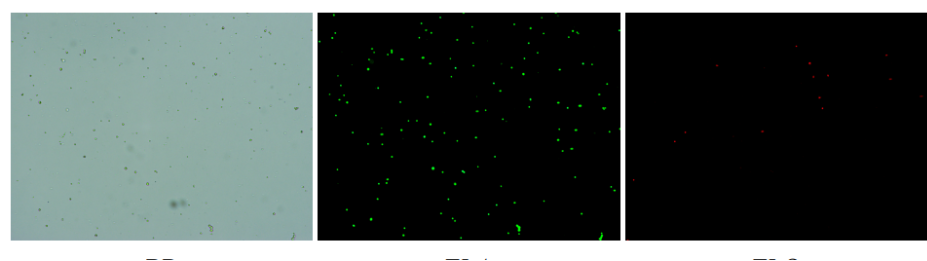

人肝癌樣本,懸液背景干凈,活性91.69%,結團率6%